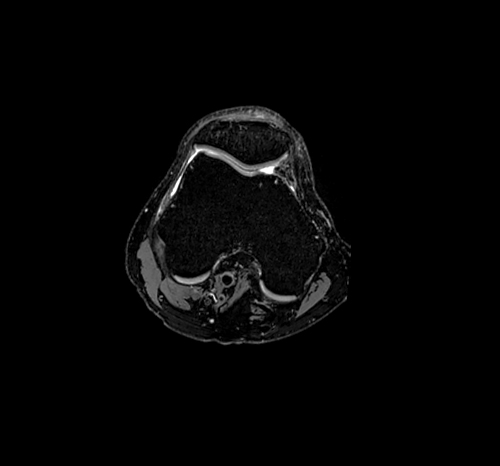

Ο Magnetom Lumina διαθέτει πολυκάναλα πηνία τελευταίας τεχνολογίας για υψηλής διαγνωστικής αξίας απεικόνιση της ανατομίας και της λειτουργίας όλων των περιοχών του ανθρωπινου σώματος. Διαθέτει δυνατότητα πραγματοποίησης όλου του φάσματος των εξετάσεων Μαγνητικής Τομογραφίας, όπως νευρολογικών, ογκολογικών, μυοσκελετικών, καρδιολογικών εξετάσεων, καθώς και ειδικές εξελιγμένες τεχνικές απεικόνισης. Κάποιες από αυτές της ειδικές εξετάσεις είναι ολοσωματική μαγνητική τομογραφία, τεχνική μείωσης παρασίτων από συμβατά με μαγνητικό τομογράφο μεταλλικά εμφυτεύματα, παραμετρικοί χάρτες καρδιάς για διάγνωση αρχόμενης ισχαιμίας, στεφανιογραφία χωρίς έγχυση σκιαγραφικού, μελέτη αιμάτωσης εγκέφαλου, πολυπαραμετρική προστάτη, μαγνητική μαστογραφία, μέτρηση αιμάτωσης εγκέφαλου, μέτρηση σιδήρου και λίπους του ήπατος, δυναμική αγγειογραφία.

Απεικόνιση 3